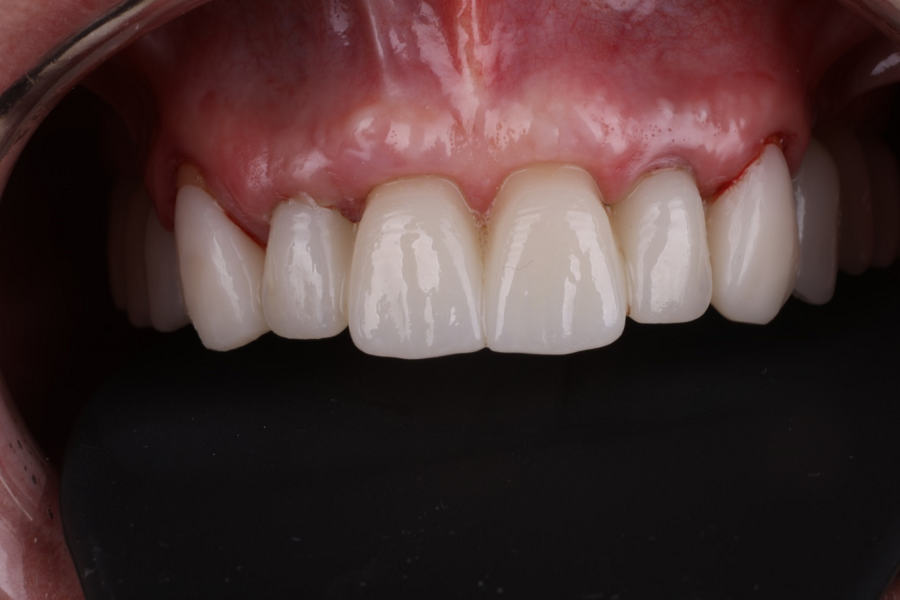

Definitive prosthetic treatment was performed after completion of implant healing with three CAD/CAM-fabricated monolithic zirconia bridges (DD cubeX2, Dental Direkt). The bridges were screwed on to BEGO titanium base abutments (Figs. 14–16). Good fit of the prosthetic superstructures was displayed in the radiograph after placement (Fig. 17). The two-year follow-up examination in July 2019 revealed excellent aesthetic and clinical soft-tissue conditions (Figs. 18–20). No radiographic bone loss had occurred at the implant sites (Fig. 21). Neither the submerged central incisors nor the distobuccal molar root displayed any signs of periapical inflammation, and the patient reported no complications. The patient’s oral hygiene had improved significantly during the follow-up period.

Fig. 14: Frontal aspect of the definitive prosthetic restorations, showing good aesthetic conditions with no signs of soft-tissue complications after insertion.